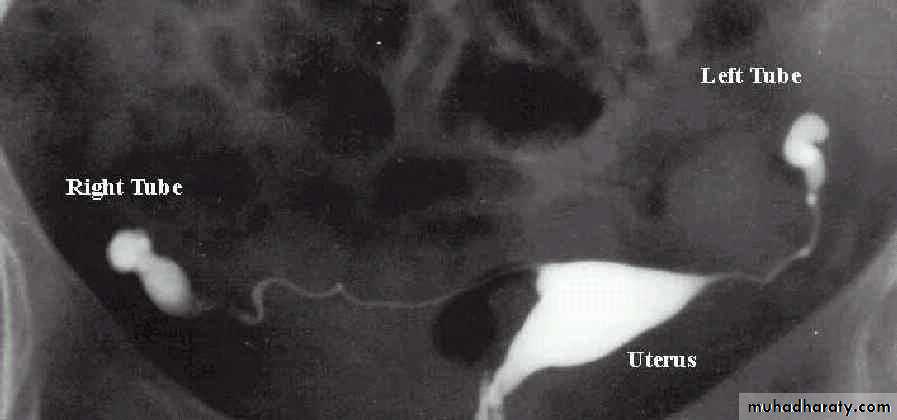

Once preliminary investigations suggest that a woman is ovulating and semen parameters are satisfactory, the next step should be assessment of tubal status. It can be assessed by three different methods:a. Hystrosalpingography

a. Hysterosalpingogram (HSG)

A radio-opaque contrast medium is injected through cervix into the uterus under X- ray control to assess uterine cavity and patency of fallopian tubes by seeing free spill into peritoneal cavity. It is usually carried out in first 10 days of menstrual cycle in order to avoid disruption of an early pregnancy. It will cause period-like pain.

Test preceded by taking cervical swabs for Chlamydia in any patient before carrying intrauterine instrumentation. Some physicians prescribe several days of antibiotics for their patients to attempt to reduce the risk of infection after HSG.